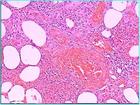

皮下脂肪层由脂肪细胞所构成的小叶及小叶间的结缔组织间隔所组成。按炎症的主要发生部位可将脂膜炎分为小叶性脂膜炎及间隔性脂膜炎两大类。脂膜炎是一谱宽的综合征,随临床特点、关连的疾病、病理改变不同而可分为不同亚类。诊断除尽量发现引起的疾病和病原外,最早期新鲜的活俭,切除足够量的标本,行系列性病理切片(以定间隔性、小叶性或混合性),很为重要。

2 .病理诊断:皮肤结节活检,其组织病理学改变是诊断的主要依据,它可分为三期:

( 1 )第一期(急性炎症期):在小叶内脂肪组织变性坏死,有中性粒细胞、淋巴细胞和组织细胞浸润,部分伴有血管炎改变。

( 2 )第二期(吞噬期):在变性坏死的脂肪组织中有大量巨噬细胞浸润,吞噬变性的脂肪细胞,形成具有特征性的 " 泡沫细胞 " 。

( 3 )第三期(纤维化期):泡沫细胞大量减少或消失,被纤维母细胞取代;炎症反应被纤维组织取代,最后形成纤维化。